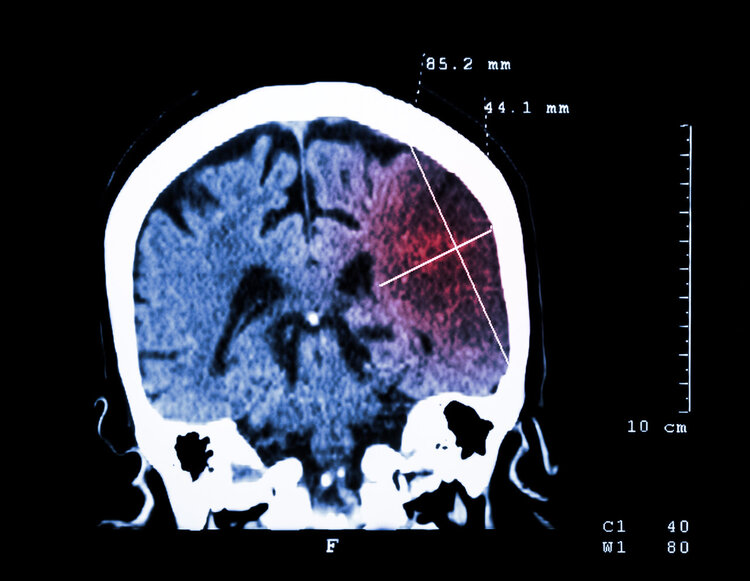

结果上个月 , 张先生因为晕倒被送进医院 , 检查结果显示他的原发性高血压病已达到了极高危的三级 , 还伴有脑梗塞、高脂血症、通风、脂肪肝和眼底出血等问题 。